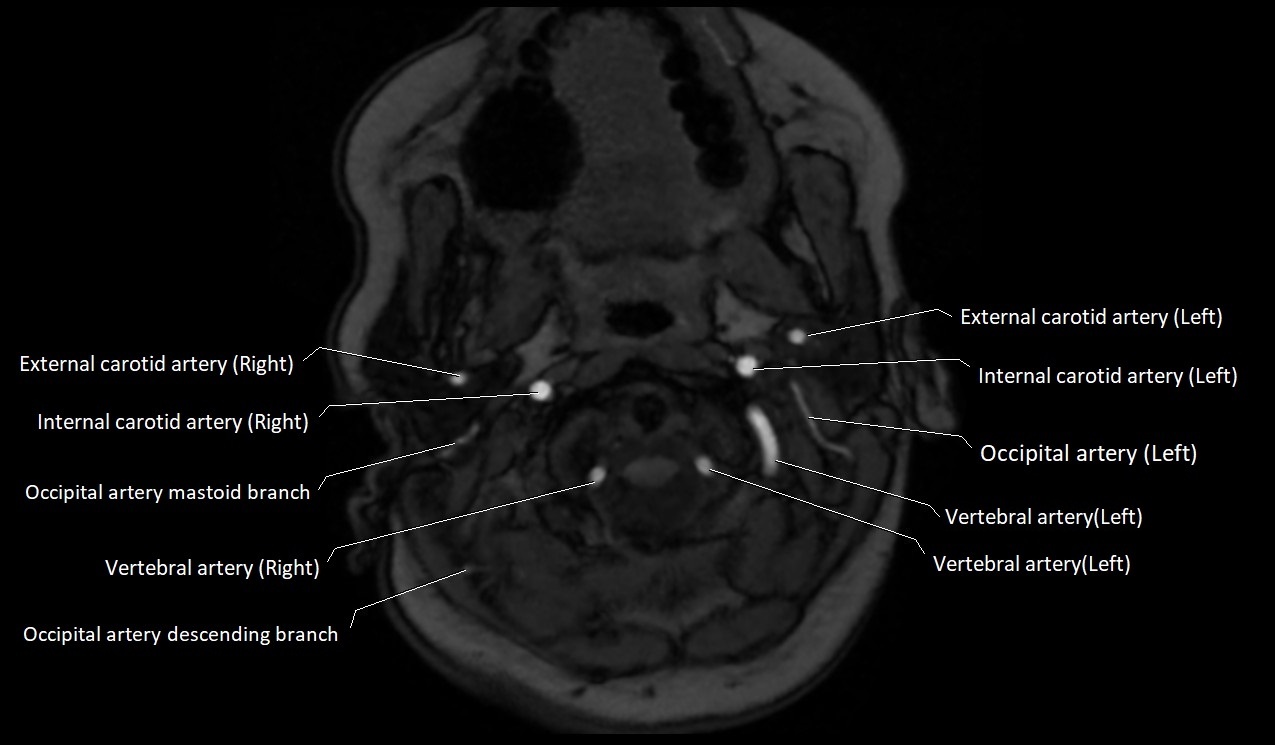

MRI Appearance:

• T1-Weighted Images:

• Appears as a tubular, hypointense (dark) structure relative to muscle

• May show flow void if the blood flow is fast

• T2-Weighted Images:

• Typically hypointense or isointense to muscle, but can be hyperintense if slow flow or stasis is present

MRI images